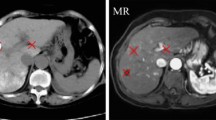

Cross-sequence magnetic resonance image (MRI) registration and segmentation are two essential steps in a variety of medical image analysis tasks. And have attracted considerable research interest. However, they remain challenging due to domain shifts between different sequences. This study is aiming at proposing a novel method via disentangled representations, latent shape image learning (LSIL), for cross-sequence image registration and segmentation.

Images from different sequences were firstly decomposed into a shared domain-invariant shape space and a domain-specific appearance space via an unsupervised image-to-image translation approach. A latent shape image learning model is then built on the disentangled shape representations to generate latent shape images. A series of experiments including cross-sequence image registration and segmentation were performed to qualitatively and quantitatively verify the validity of our method. Dice similarity coefficient (DSC) and 95th percentile Hausdorff distance (HD95) were adopted as our evaluation metrics.

The performance of our method was evaluated based on 2 datasets total of 50 MRIs. The experimental results showed the superiority of the proposed framework over the state-of-the-art cross-sequence registration and segmentation approaches. The proposed method shows the mean DSCs of 0.711 and 0.867, respectively, in cross-sequence registration and segmentation.